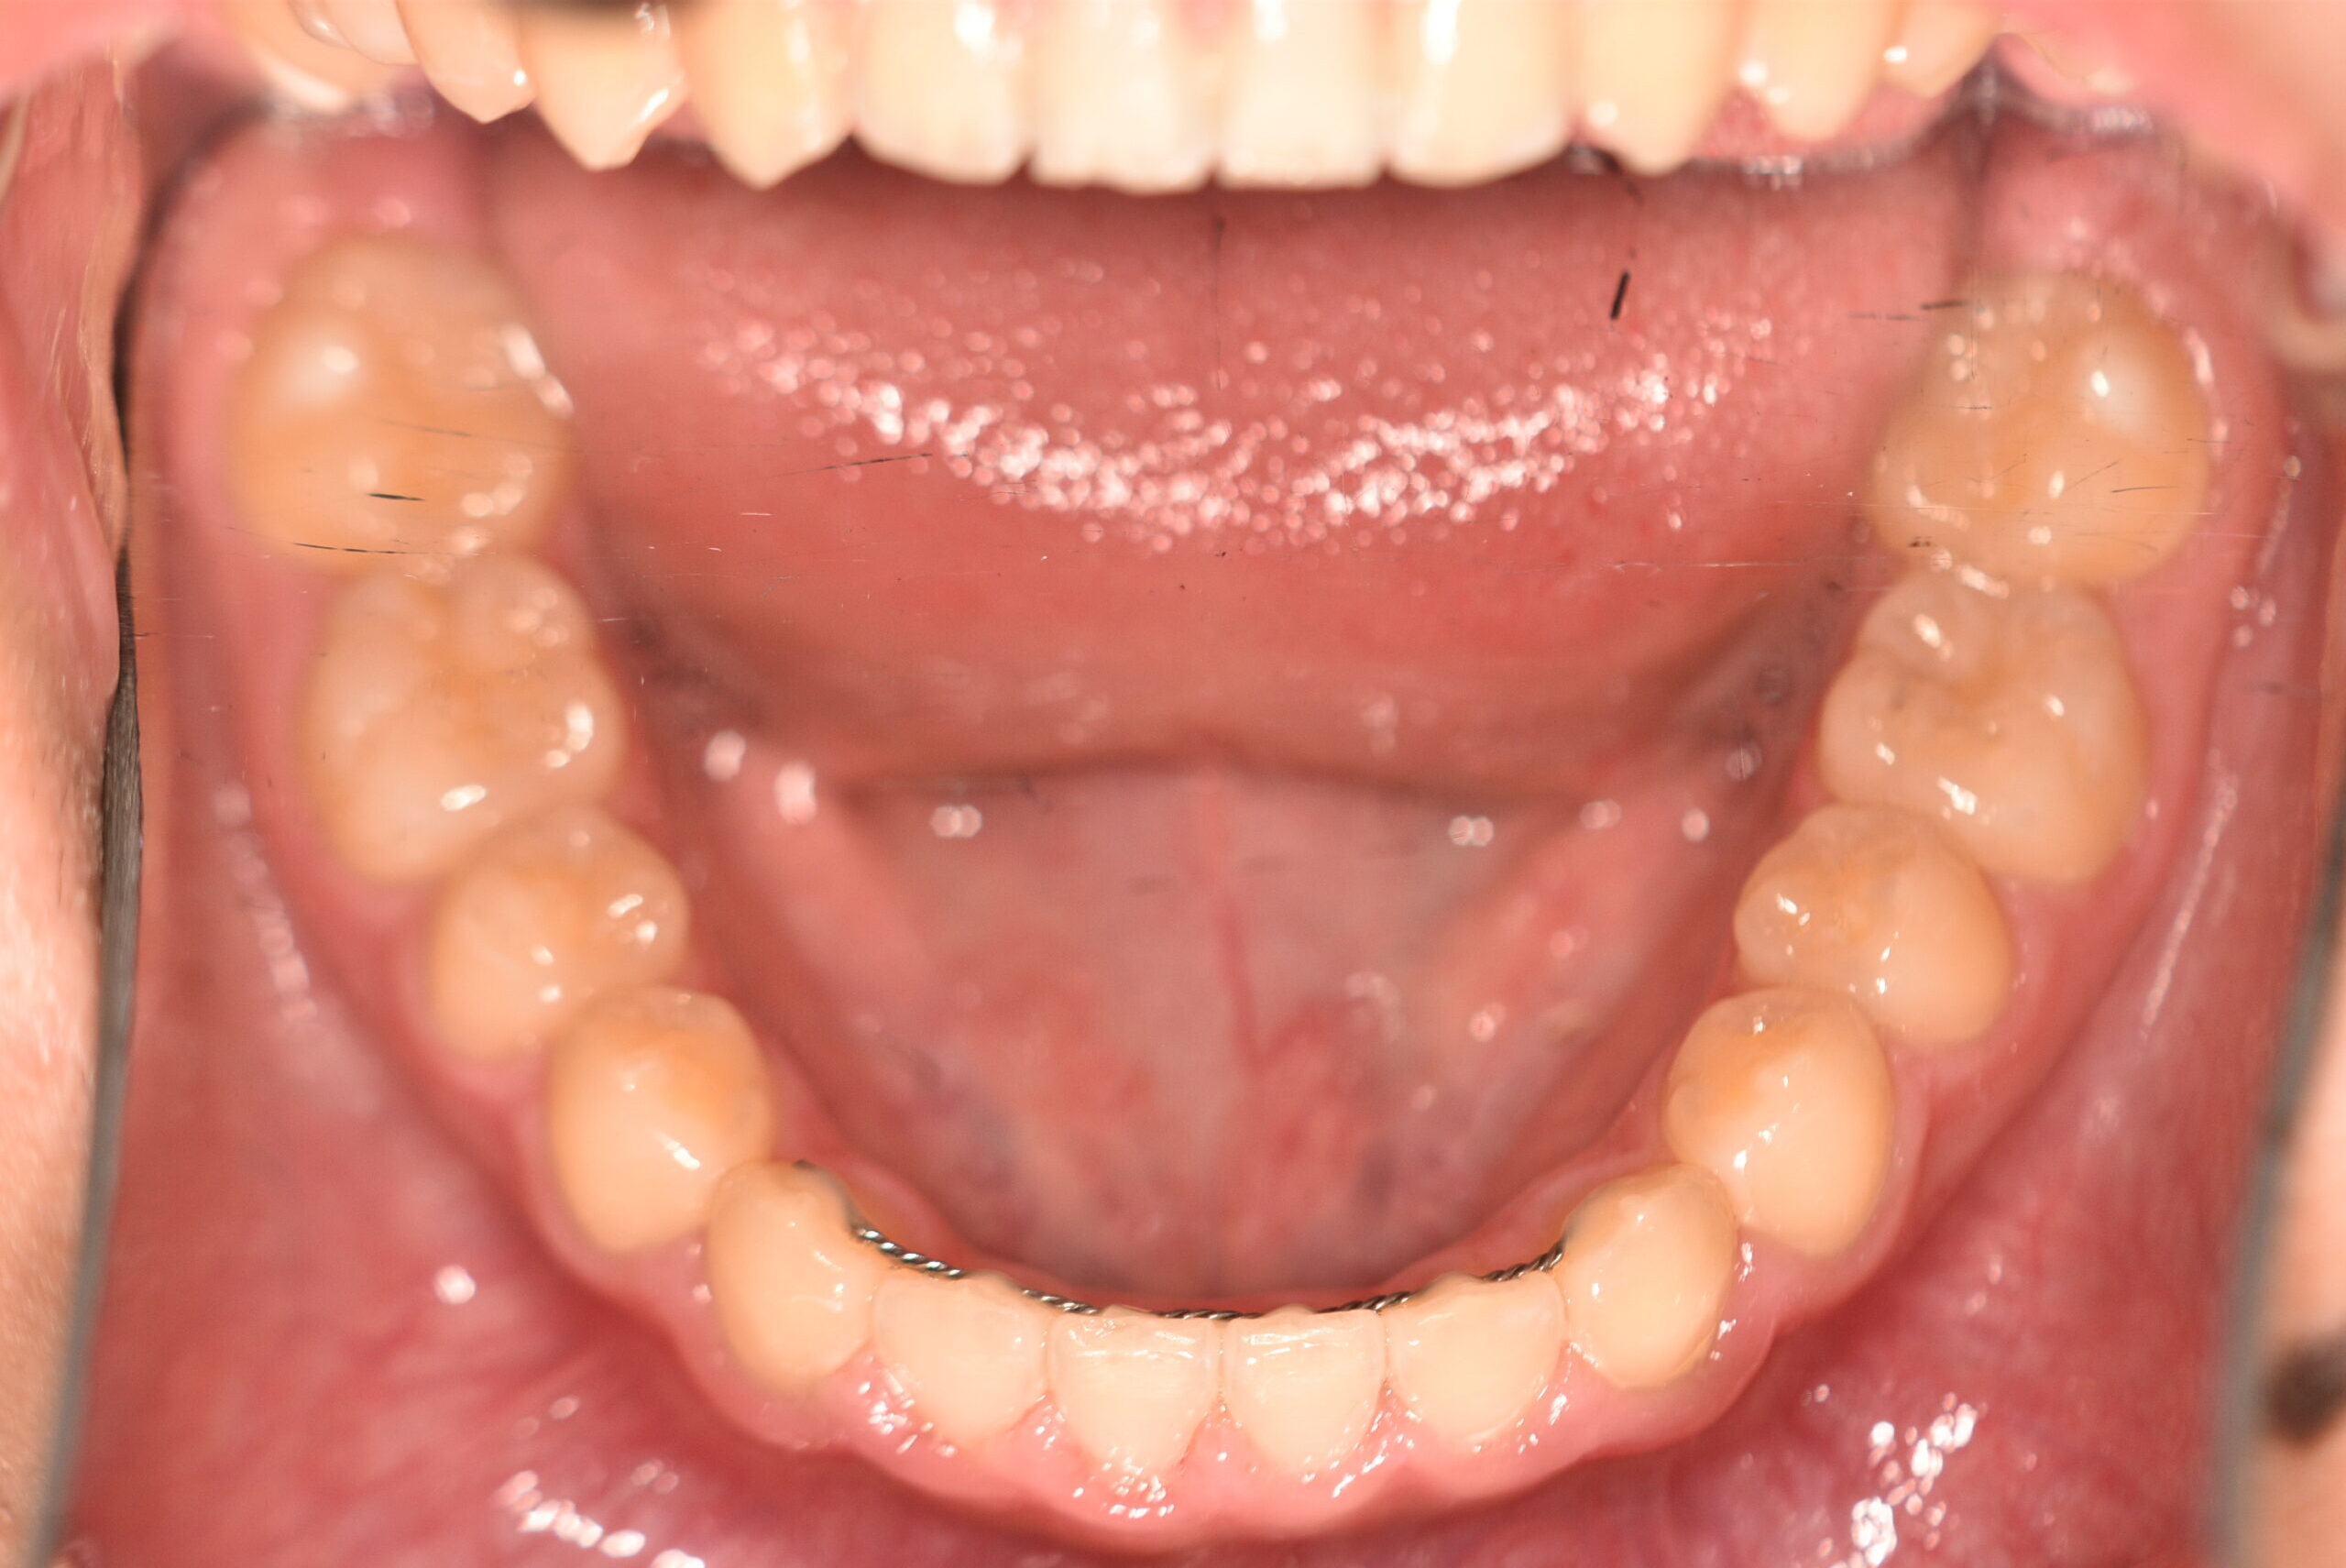

| 治療内容の詳細 | 初診時6歳の男性で、受け口を気にされ来院されました。 検査の結果、反対咬合を伴うアングルⅢ級不正咬合と診断しました。 治療としては、初期段階の治療として、機能的矯正装置で鼻呼吸の獲得と舌の位置や口唇の閉鎖といった筋機能習癖の改善を行い、上顎前方牽引装置を使用し上顎骨の前方方向への発育を誘導し、反対咬合の改善を行いました。 永久歯列に交換後、非抜歯の上、セルフライゲーションブラケット装置(デーモンシステム)で歯の配列と咬合関係の改善を行いました。 治療期間は、7年3ヶ月でした。 |